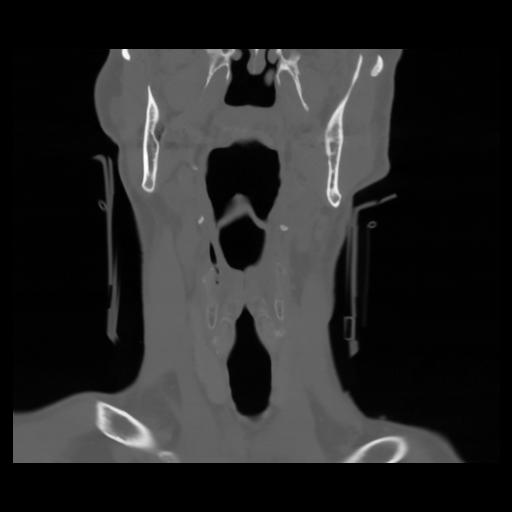

13 P.BLANDAS,,Coronal,2.000,P.BLANDAS,Coronal,